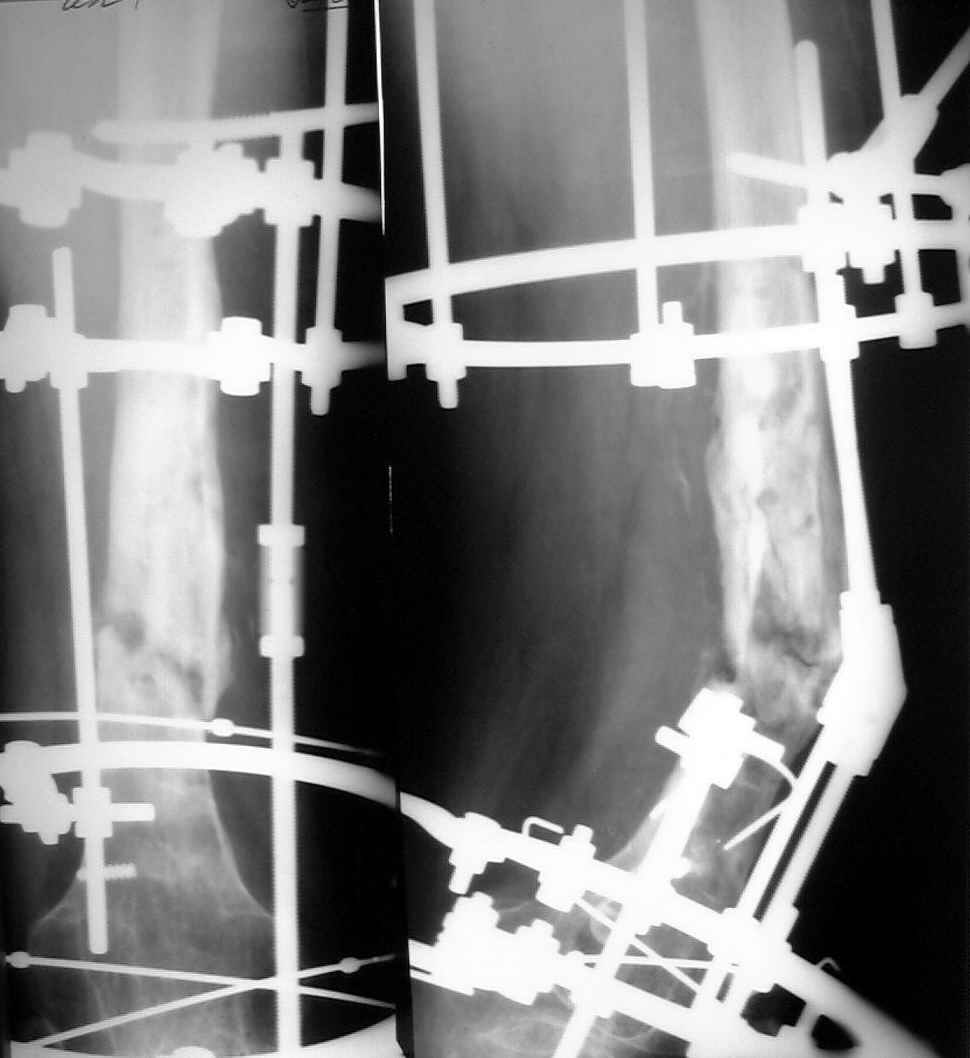

Не сформировалось у нас убежденности в целесообразности мобилизующей операции в один этап с остеосинтезом. Решили пойти по максимально щадящему пути. Первым этапом наложили аппарат. Снимок (см. приложение) сделан в положении максимально возможной коррекции оси, достигаемой одномоментно исправлением "об коленку" с ручным растягиванием колец сзади. Варус удалось убрать, а вот антекурвацию, от греха, лучше устраним дозированно, дней за 7-10. Потом планируем антеградный закрытый интрамедуллярный остесинтез. Буду признателен за отклик.

Кликните для загрузки файла 006.jpg

42KB (43081 bytes)